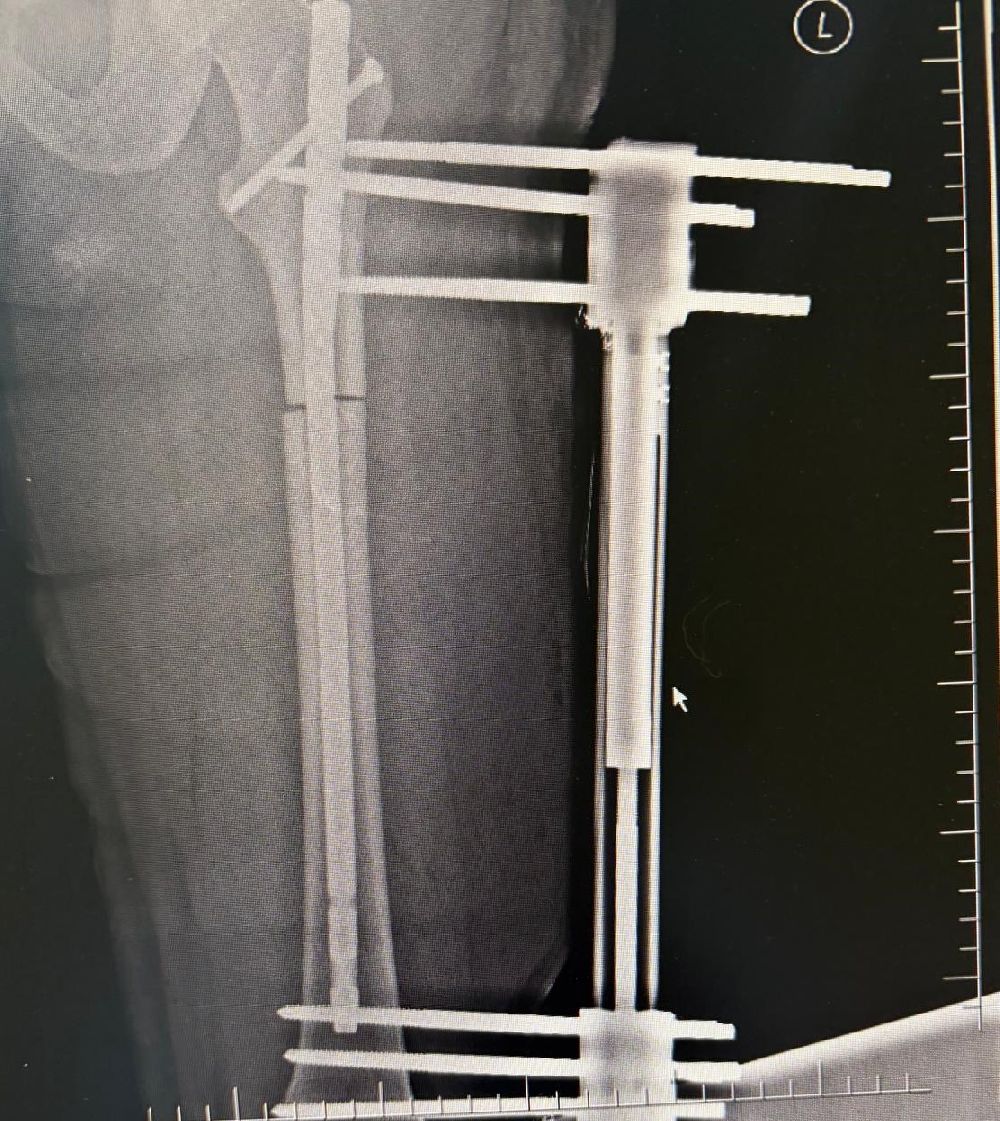

Denizli'de yaşayan 39 yaşındaki M.G., boyunun 1.58 olmasından kaynaklı fiziksel ve bedensel sorunların yaşadığını, daha uzun bir görünüme kavuşmak ve yaşam kalitesini artırmak amacıyla Denizli Özel Tekden Hastanesi'ne başvurdu. Hasta uzun yıllardır boyunun kısalığının gerek günlük yaşamda gerekse sosyal çevresinde çeşitli zorluklara yol açtığını dile getirdi. Aynı zamanda duruş bozukluğu ve bazı fiziksel rahatsızlıklar nedeniyle uzman bir hekime danışma kararı alan M.G., hastanenin Ortopedi ve Travmatoloji bölümünde görev yapan iki uzman doktora başvurdu. Ortopedi ve Travmatoloji Uzmanı Prof. Dr. Mahmut Argün ve Op. Dr. Necip Özateş tarafından detaylı şekilde muayene edildi. Doktorlar tarafından yapılan değerlendirmeler sonucu, hastanın ortalama 10 santimetre daha uzamasının mümkün olduğu belirtildi.

Ameliyat aşamasının ardından gerçekleşen süreci tek tek dile getiren Ortopedi ve Travmatoloji Uzmanı Prof. Dr. Mahmut Argün, "Hastamız 1.58 boyunda olması nedeniyle sürekli boyunun kısalığından dolayı hem fiziksel hem de bedensel rahatsızlıkların olduğunu dile getirdi. Israrla boyunun uzatılmasını bizden talep eden hasta 2 aşamalı olunması gereken muayeneyi 1 aşamalı olmasını istedi. Sol tarafından başlayarak hem femur hem de tibia 5 ila 6 santimetre arasında uzatmayı planladık. Hastamızı ameliyata alıp bu işlemleri gerçekleştirdik. Hasta şuanda uzatma işlemlerinin yapılabilmesi için malzeme yerleştirme aşamasını gerçekleştirdik. Ameliyattan 10 gün sonra uzatma işlemlerini başlayacağız. Uzatma işlemleri yaklaşık 60 gün sürecek. Uzatma işlem süreci geçtikten sonra işlemi durdurup kaynaması için 2-3 ay bekleyeceğiz. Ardından ise hastanın üzerinden malzemeleri yaklaşık 150-200 gün arasında çıkaracağız. Bu tarz işlemler meşakkatli ve özen isteyen ameliyatlar" diye konuştu.

Uzama sürecinde her gün 1 milimetre olmak üzere kurulan mekanizmanın başladığını dile getiren Ortopedi ve Travmatoloji Uzmanı Op. Dr. Necip Özateş, "Her gün 1 milimetre olmak üzere, üzerindeki mekanizma üzerinden hem uyruk kemiği hem kaval kemiği uzatılmaya başlıyor. Hem bu şekilde kemik uzaması hem de bu esnada kemik kaynaması aynı anda olduğu için daha kontrollü bir işlem oluyor. Hedef uzunluğa ulaştığımızda uzatma işlemini sonlandırıyoruz. Sonrasında da kemiğin kaynaması sürecine geçiyoruz" dedi.

İlk 4 hafta üzerine bastırmadıklarını ardından ise kontrollü bir şekilde sürecin ilerlediğini belirten Op. Dr. Necip Özateş, "İlk etapta ameliyatın erken dönemlerinde ilk 4 haftaya kadar üzerine bastırmıyoruz. Ondan sonraki günlerde yavaş yavaş hasta koltuk değnekleri yardımı ile destek alarak üzerine basmaya ve günlük yaşantısına daha rahat devam etmeye başlıyor. Yapılan ameliyat bir vatandaşın günlük hayatına etkileyen bir şey değil. Bu süreç hastanın da bilgisi dahilinde özen ve biraz daha sabır gerektiren bir süreç. Bu konuda hastayla fikirde varıldığı zaman gayet iyi sonuçlar elde ediyoruz" ifadelerini kullandı.